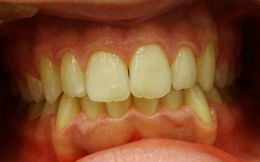

Caso ortodontico complesso in paziente adulto; prima classe scheletrica tendente alla biprotrusione. Terapia proposta: apparechhio fisso miniunitwin utizzo delle frizione differenziato. Teccnica avanzata di gestione della frizione.

Caso impegnativo di grave affollamento in pz biprotruso che ha richiesto la estrazione di 14 24 34 44